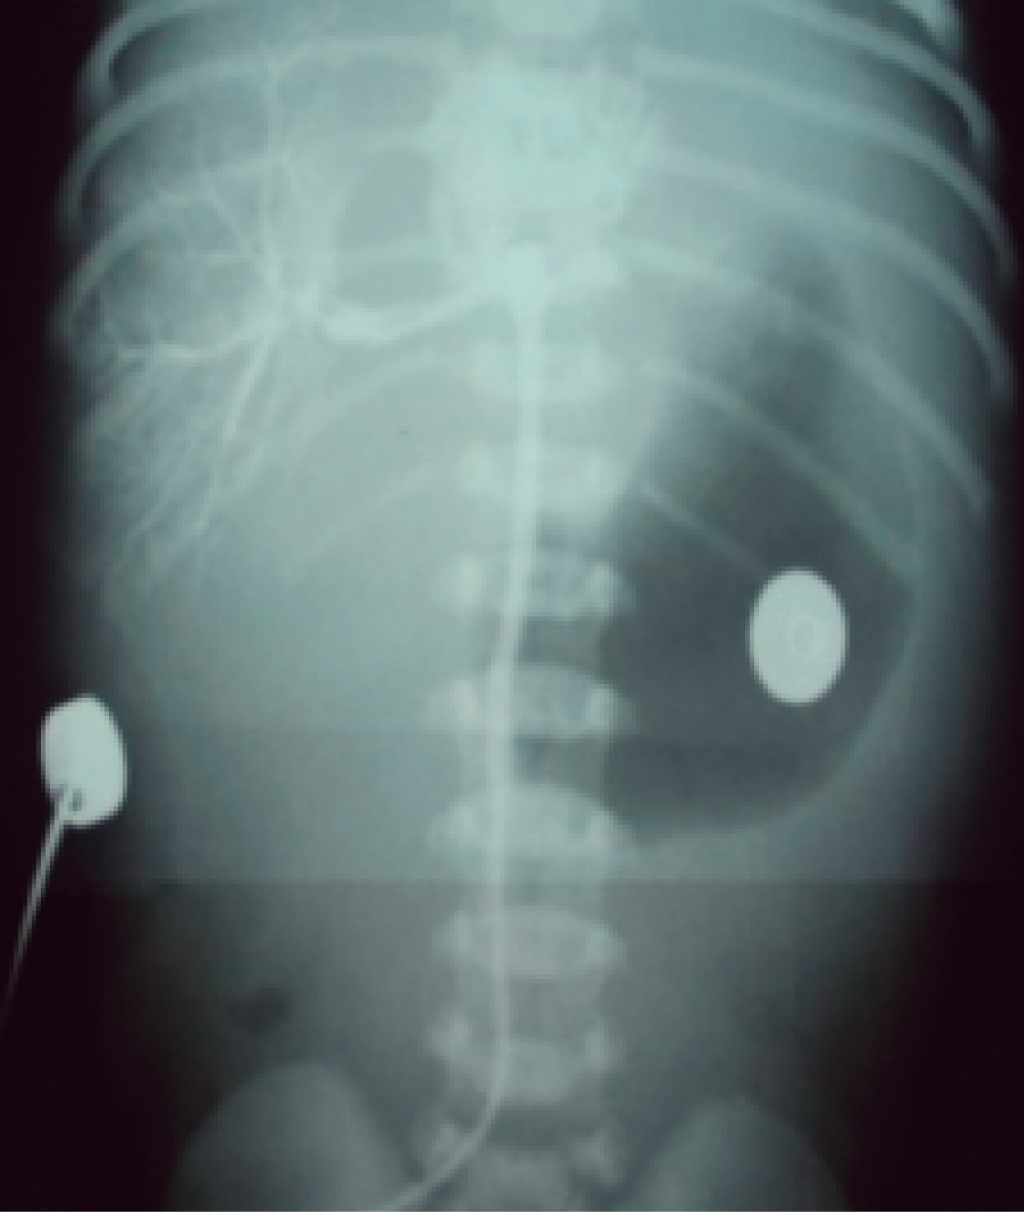

El trayecto que normalmente debe recorrer el catéter venoso umbilical para que quede en la posición correcta es el siguiente: se introduce por la vena umbilical, llegando al primer receso venoso umbilical, lugar al que llegan las venas portales derecha e izquierda y donde inicia el conducto venoso de Arancio con una longitud de 1 a 2 cm y posteriormente llega al segundo receso umbilical, lugar al que llegan las venas hepáticas derecha e izquierda, y en seguida pasa a la vena cava inferior para terminar en la entrada de la aurícula derecha (Figuras 2 y 4). Generalmente, el catéter sigue el trayecto descrito; sin embargo, sucede en ocasiones que se puede desviar a múltiples lugares según la vena por la cual se deslizó y, por lo tanto, queda en posición anómala, lo que podría provocar múltiples complicaciones, por lo que idealmente se debe solicitar una radiografía toracoabdominal al término de la colocación del catéter para corroborar su posición y, de ser necesario, realizar las correcciones convenientes antes de fijarlo y de retirar el campo estéril. Una vez retirado el campo estéril, un catéter mal posicionado que se encuentre por arriba del sitio correcto sí podrá ser retirado algunos centímetros para dejarlo en posición correcta. Cuando la punta del catéter queda por debajo del hemidiafragma derecho, ya sea en el trayecto normal o en una de las venas del sistema venoso umbilical, no podrá introducirse para dejarlo en una posición correcta, ya que el riesgo de infección es alto, pero sí podrá retirarse algunos centímetros para dejarlo en alguno de los vasos del trayecto normal (Figura 5). Recordar que cuando la punta del catéter venoso queda en cualquier sitio del trayecto normal nunca se podrán manejar soluciones hiperosmolares (> de 800 mOsm/L), ante el peligro de causar daño al endotelio vascular e incluso perforación del vaso. El catéter venoso umbilical puede tener una posición baja, la cual se sitúa de 2-4 cm por debajo de piel de pared abdominal. Esta posición baja se coloca al momento del nacimiento, cuando el recién nacido se encuentra en malas condiciones y requiere de una infusión rápida de líquidos, medicamentos o hemoderivados, no se debe introducir en estos momentos de la reanimación más centímetros, porque se puede situar el catéter en una posición incorrecta y ésta podría hacer que se dirija a la vena portal derecha, infundir los productos al hígado y causar daño importante a este órgano (Figura 6).7

• 4. Laceración hepática, quistes hepáticos, acumulación de líquido en el hígado, ascitis, necrosis hepática y perforación de un vaso tras la colocación (Figuras 6 y 17).4,5